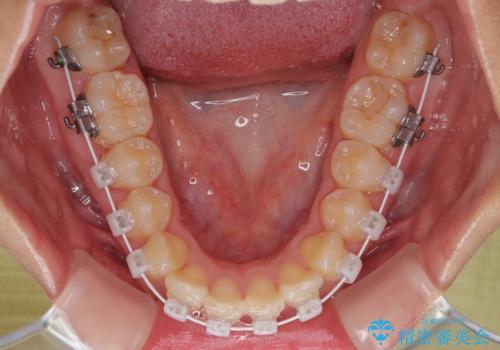

・アーチを側方に拡大して歯が並ぶスペースを確保

・抜歯は避け、非抜歯での対応

・目立ちにくい審美装置による矯正

・治療期間をできるだけ短縮するために、綿密な装置管理と協力体制を構築